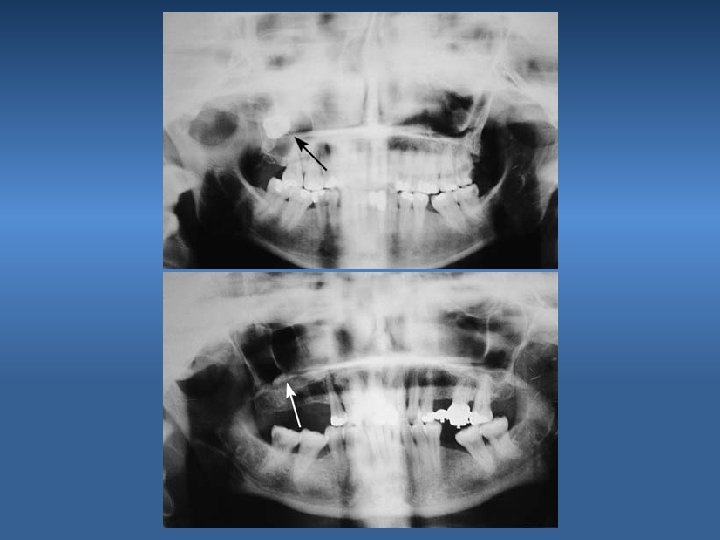

3. Fracture of the Mandible Cause Excessive force Prevention Proper bone removal & controlled force

Photoelastic model of the mandible, showing the development of stress during a luxation attempt of the third molar when insufficient bone has been removed from the tooth peripherally